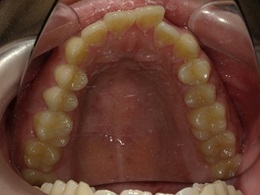

上顎治療前

上顎治療後